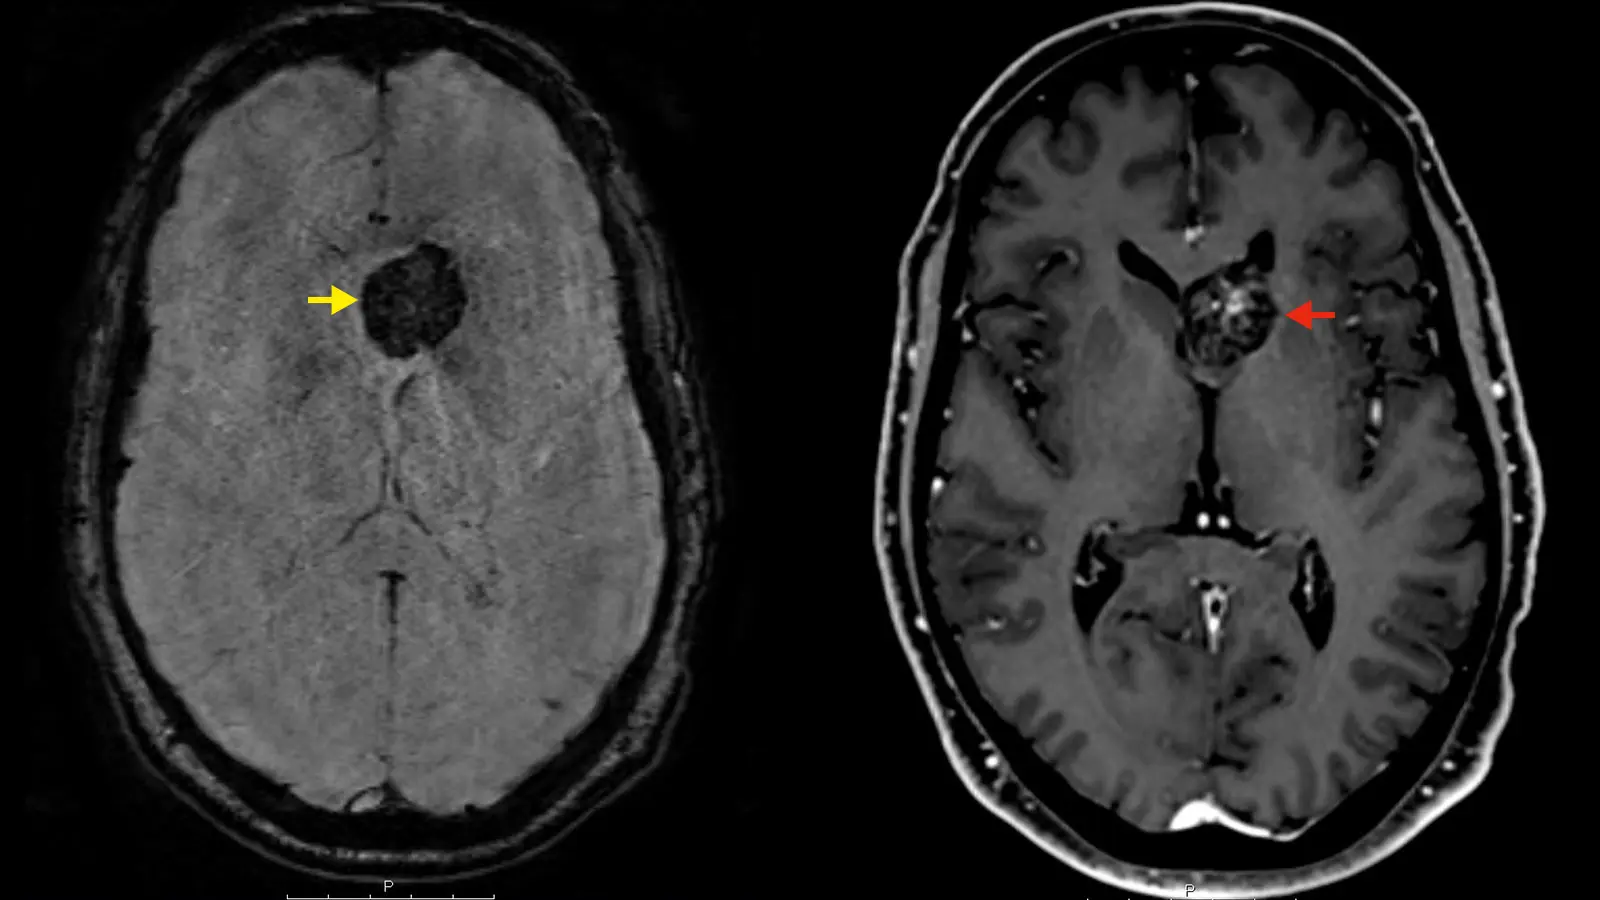

Die Diagnose von Kavernomen erfolgt in der Regel durch eine Magnetresonanztomographie (MRT). Diese bildgebende Untersuchung ermöglicht es den Ärzten, die Größe, Lage und Aktivität des Kavernoms zu beurteilen.